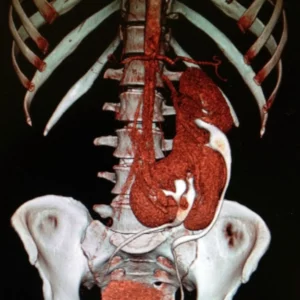

CT Angiogram

Vascular Anomalies of the Kidney

Vascular malformations of the kidney are disease processes that involve renal veins and arteries and include congenital arteriovenous malformations (AVMs) and arteriovenous fistulas. AVMs are congenital communications between arteries and veins with a vascular nidus that bypass the capillary bed.